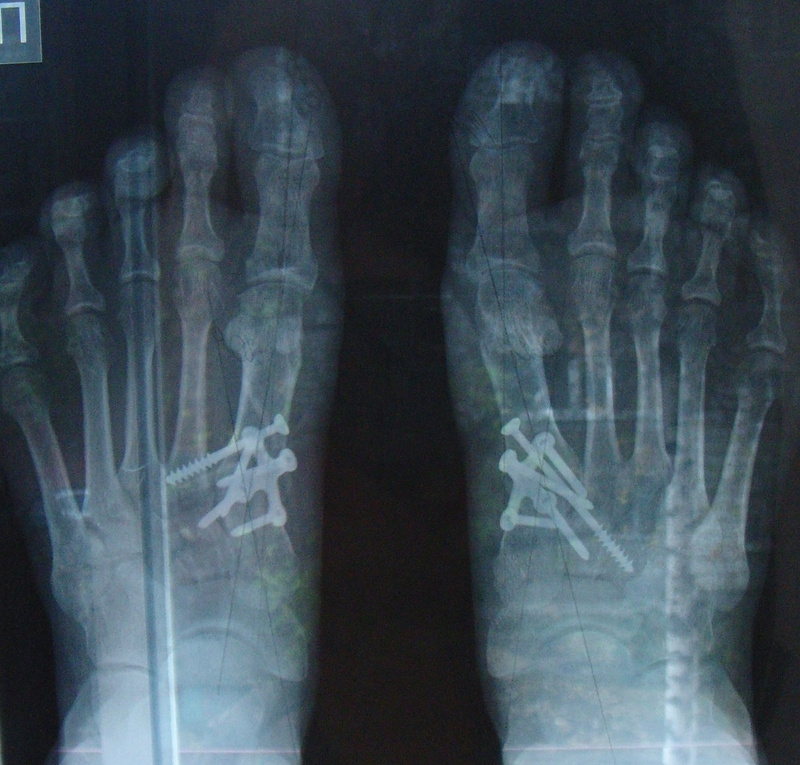

Оперировал Пахомов, хотя записывалась я у другого, они как-то все поменяли в последние дни. У меня в каждой ступне по 2 винта (скрепляют большой палец и кость в стопе) - это была остеотомия. Шрамы на мой взгляд не бросаются в глаза (может завтра сфотаю и выложу до и после). Фитнесом я занималась, с этим все нормально. Правда первую зиму после операции я лыжный сезон пропустила, хотя запрещено мне не было. Ещё мне говорили, что можно после заживления костей вытащить винты (или у кого пластины), но естественно проходить оперативное вмешательство опять я не собиралась. По поводу восстановления: недели полторы после выписки по дому я каталась на стуле с колесиками - жалела себя и не ходила:)... потом месяц ходила в спецобуви (о ней писали выше), выглядело это по дурацки, но уж точно лучше костылей с гипсом. Потом ещё месяца 3 ходила в удобной мягкой обуви на плоской подошве, вот и всё. Спрашивайте что интересует, а то у нас реально об этом мало информации.Ответ на сообщение Re: Косточки на ногах пользователя AverAnna